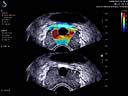

• TriVue – simultánní real-time zobrazení 2D/CFI (barevný doppler)/SWE

• ShearWaveTM Plus Elastografie (SWE)